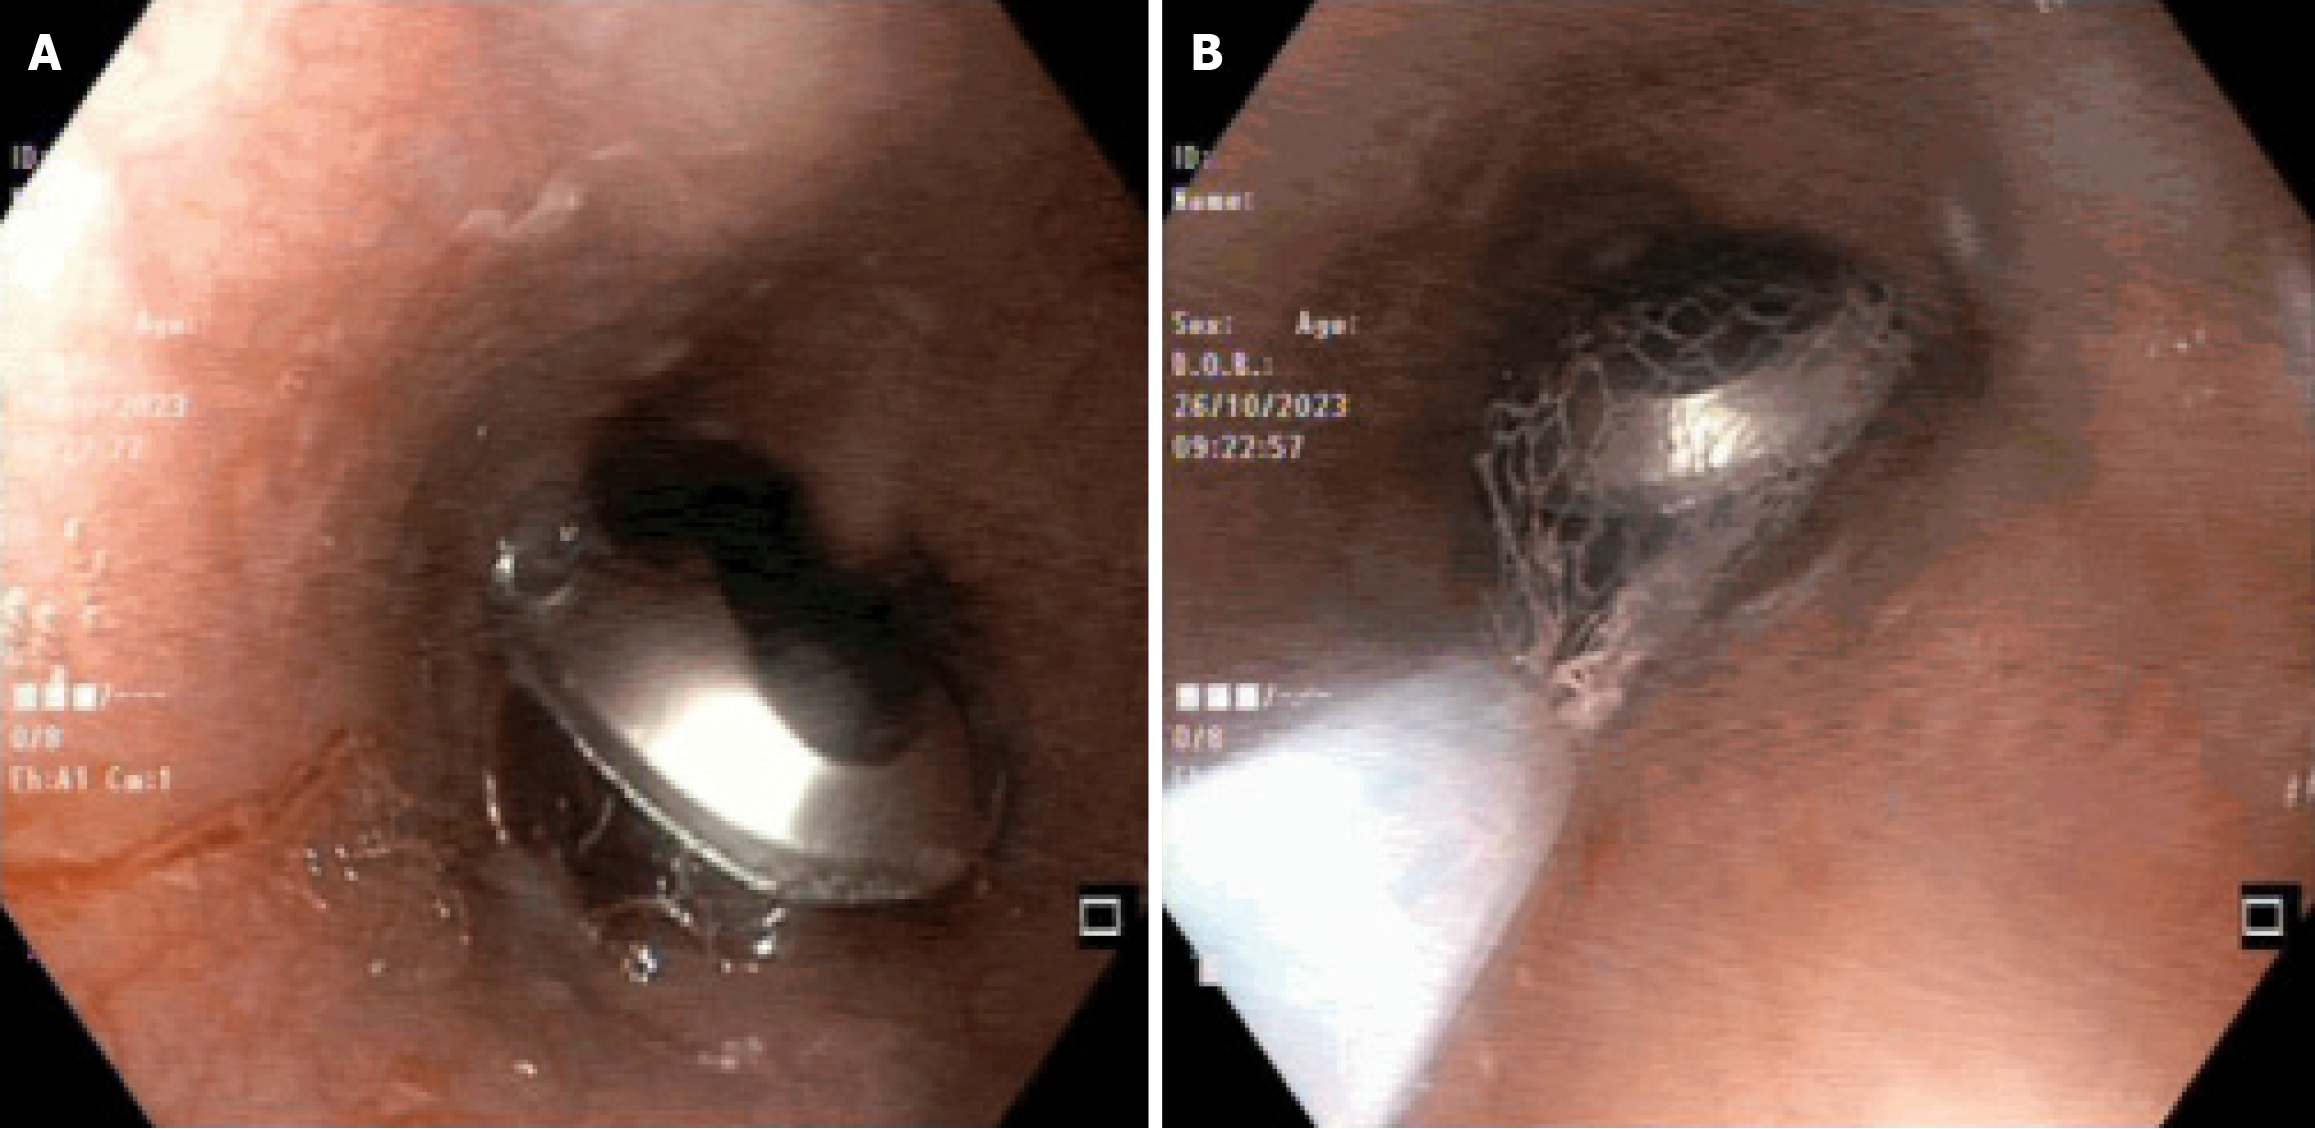

Selecting the appropriate instrument is essential for the effective removal of foreign bodies, depending on their nature and location. Coins can be easily extracted using forceps, while soft meat boluses are best removed with a retrieval basket. In cases where pins have penetrated the bowel wall, a snare is the preferred tool for safe removal[7]. Forceps are among the most commonly used tools, with rat-tooth forceps being the standard choice, while alligator-tooth and shark-tooth forceps offer additional versatility. Retrieval forceps with 2 to 5 prongs are effective for grasping soft objects like food boluses but lack the secure grip needed for harder or heavier foreign bodies. Biopsy forceps, with their small opening width, are best suited for retrieving small and soft objects. Baskets, such as the Dormia basket with three, four, or six wires, are ideal for round foreign bodies, providing a secure grip. Polypectomy snares and retrieval nets are also widely used. Polypectomy snares, available in sizes ranging from 10 to 30 mm, are inexpensive and effective, while retrieval nets, though more costly, are particularly useful for extracting flat or delicate objects like coins, disc batteries, and magnets[11]. Small intestinal foreign bodies can be removed via balloon-assisted enteroscopy[17]. Figure 3 illustrates pill packet dislodgement in esophagus, which was removed safely using Roth net. The Roth net provided secure coverage to safely extract a sharp, rounded pill packet from the esophagus.

Figure 3

Figure 3 Demonstrates the use of Roth net in removing foreign body (pill packet) from the esophagus. A: Pill packet is seen dislodged in mid esophagus, with its sharp edges eroding the mucosal lining; B: Roth net is being used endoscopically to retrieve the pill packet. Picture is taken from Endoscopy suite, section of Gastroenterology, Aga Khan University Hospital Karachi.